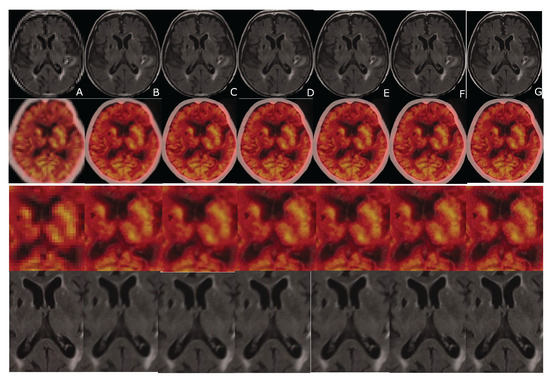

4. Compressively Sensed CT/PET Signals

5. The Super-Resolution Algorithm vs. Image Registration Issues

6. Evaluation

7. Results